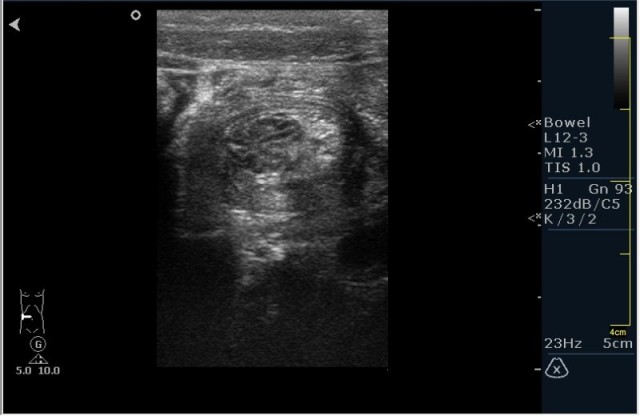

Ребёнок с болями в животе.

инвагинация! :!:

На представленных сонограммах определяется типичная "мишень" или "кокарда" (7ая и 8ая сонограмма сверху), которая при продольном сканировании превращается в "телескоп" (сонограммы 3 & 4). Все это указывет на инвагинацию кишечника (илео-цекальную). Причиной явилось лимфаденопатия брыжейки (которую вы указали). Увеличеные лимфоузлы вместе с инвагинатом хорошо различимы в просвете толстой кишки.

Уважаемые коллеги! Без сомнения имеет место илео-цекальная инвагинация.увеличенные овальные лимфоузлы, да еще такими гроздями характерны для мезаденита.Все зависит от развертывания клинической симптоматики.